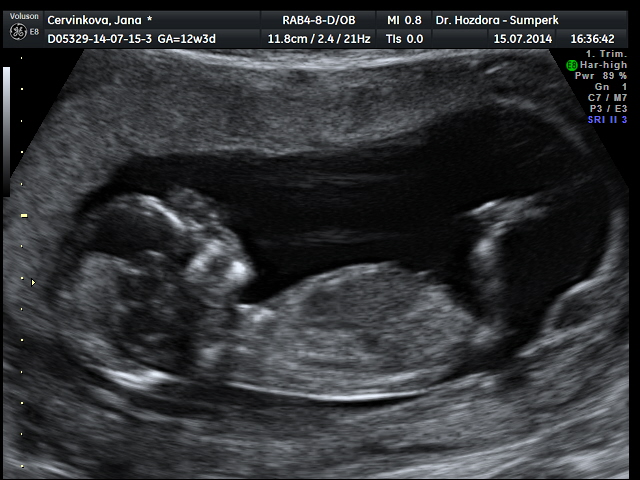

Děvčata,tak jsem doma z ultrazvuku,ten dopadl skvěle,šíjové projasnění,nosní kůstka,vše tak,jak má být. Dnes jsem 12+3,ale podle ultrazvuku už 13+1. Vypadá to pravděpodobně,že čekáme holčičku,ale jistější to bude ve 20.tt. Zítra mi sestry zavolají,jak dopadly krevní odběry...zatím mám z toho skvělý pocit. A docela mimo je i můj chlap,moc se nevyjadřoval,on ty pocity dusí v sobě,ale vypadal spokojeně. Tak zítra se screening zkompletuje a věřím,že to bude v cajku. Určitě dám zítra vědět..